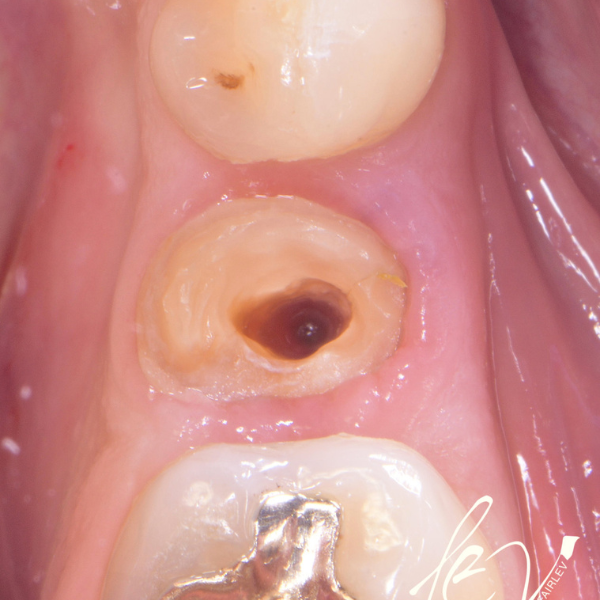

Tooth 14 slightly increased mobility, tenderness and bite pain. Suspected root fracture